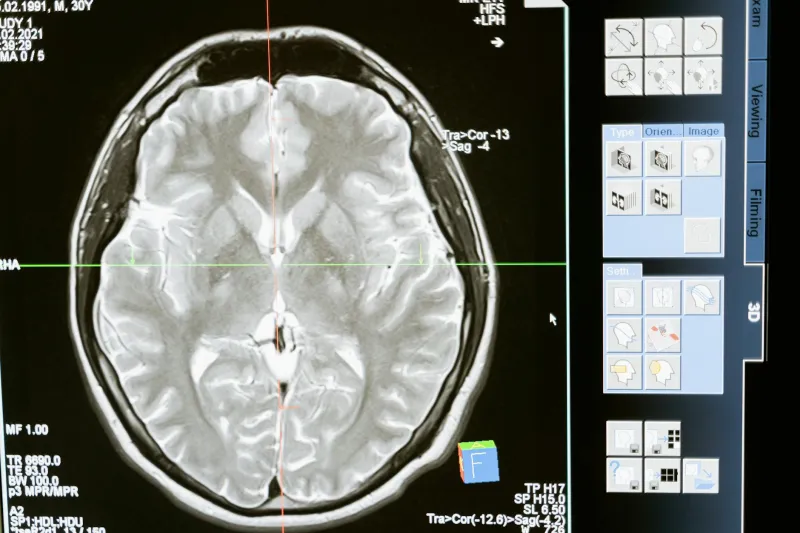

Modern brain imaging technology tells a completely different story. When neuroscientists use fMRI and PET scans to watch healthy brains in action, they see both hemispheres lighting up during virtually every task.

Solving a math problem? Both sides are active. Writing a poem? Same thing. Even activities we consider purely "left-brain" or "right-brain" involve extensive communication between hemispheres.

A 2013 University of Utah study analyzed brain scans from over 1,000 people and found no evidence that individuals preferentially use one hemisphere over another. The researchers concluded that the left-brain/right-brain theory "is not supported by our data."